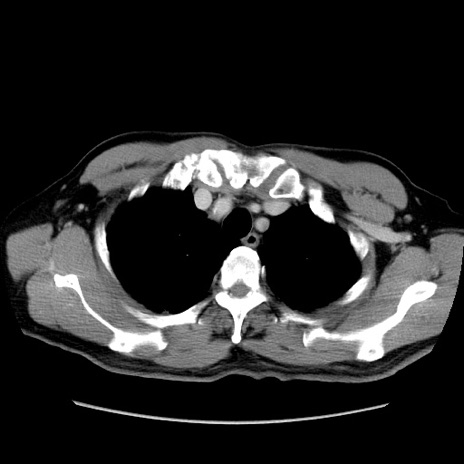

症例34(横断像)

【症例】60歳代 男性

【主訴】右鼠径部膨隆

【現病歴】1年程前より右鼠径部膨隆あり。自己にて還納可能だったため放置していた。3時間前より右鼠径部の脱出を認め、還納困難となり受診。

【既往歴】高血圧

【身体所見】右鼠径部に小児頭大の膨隆あり。弾性硬であり、用手還納は困難。左鼠径部にも膨隆を認める。脱出はなし。

【データ】WBC 15500、CRP 測定なし